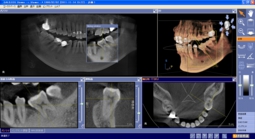

そのため、当クリニックではデンタルCTを導入し、全症例に対し事前にCT撮影をし、

埋入シミュレーションを実施しております。

デンタルCTの一例